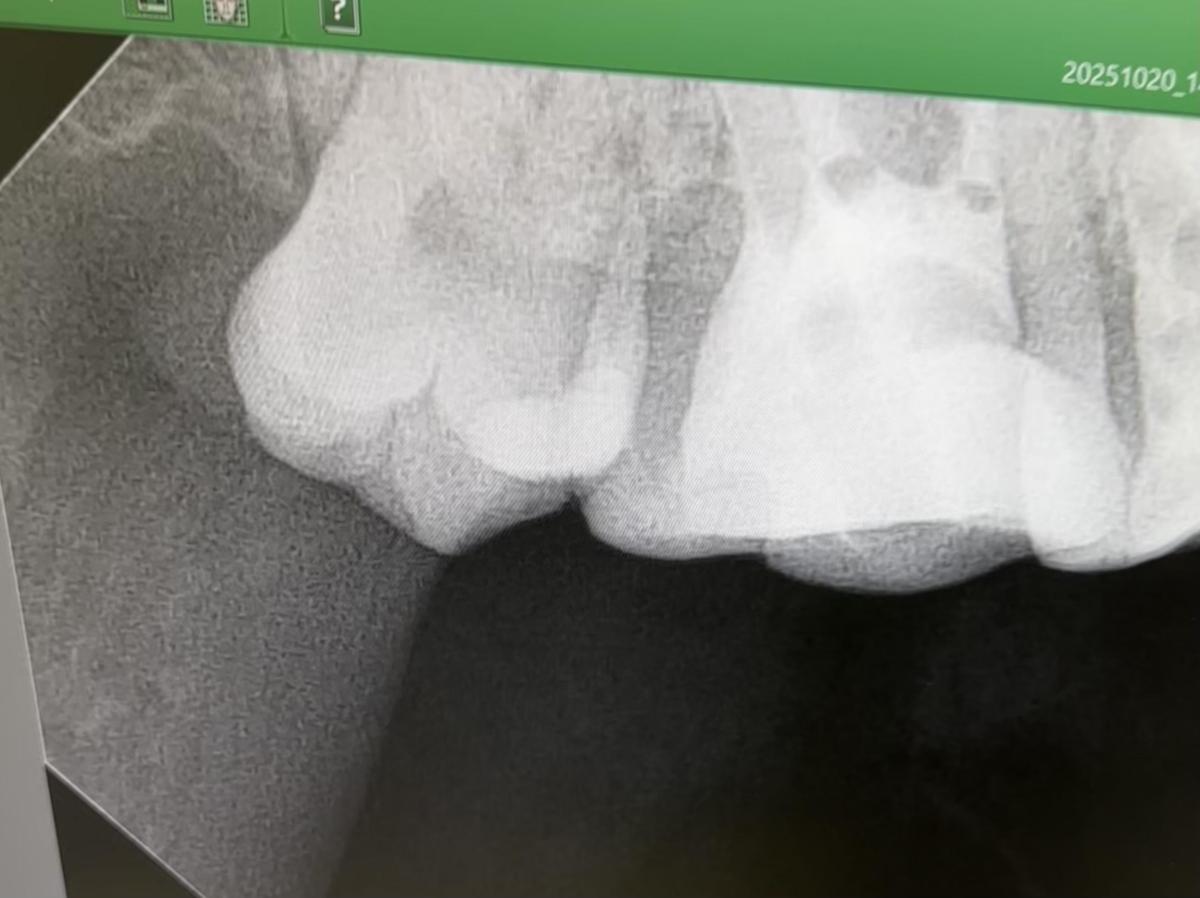

Прикладываю снимок, каналы почему-то не засняли, но сказали, что там точно пульпита/периодонтита быть не может, поэтому и не требуется их снимать.

Снимок некудышний, поэтому все вопросы остаются актуальными!